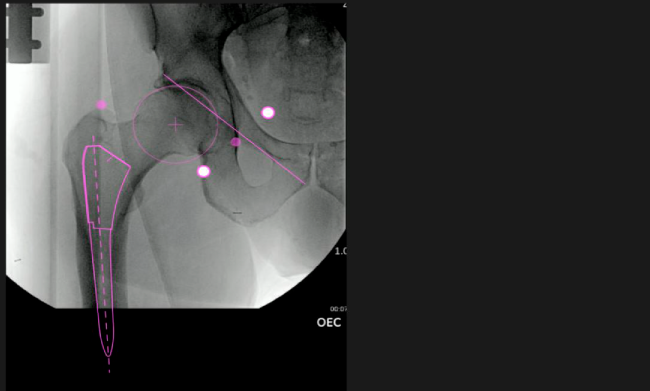

El sistema de navegación digital VELYS HIP NAVIGATION ™ para cirugía de cadera, es una tecnología innovadora y no invasiva diseñada para potencializar la toma de decisiones en tiempo real y basada en datos; aumentando la precisión y mejorando los resultados a corto, mediano y largo plazo para los pacientes.

Mayor nivel de información intraoperatoria facilita la colocación correcta de los implantes:

Inclinación y anteversión de la copa acetabular para una correcta colocación del implante.

Desplazamiento y offset para posicionamiento óptimo del componente (vástago) femoral.

Verificación de la posición deseada del implante que potencialmente puede ayudar a reducir la probabilidad de dislocación protésica y aumentar la estabilidad de la articulación.

Anotaciones digitales y herramientas de análisis de longitud de pierna.

Con tecnología ONETRIAL® que calcula automáticamente el cambio en la longitud de la pierna y el desplazamiento para todas las combinaciones de implantes en una tabla fácil de leer.